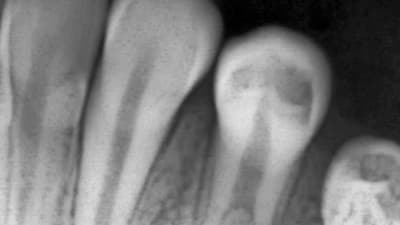

Case Reports Periodontics Techniques for Preserving Pulp Vitality in an Asymptomatic Deep Carious Lesion: A Clinical Case Study By Christine Nguyen, Sue Chhay, DDS September 01, 2022 11 min read